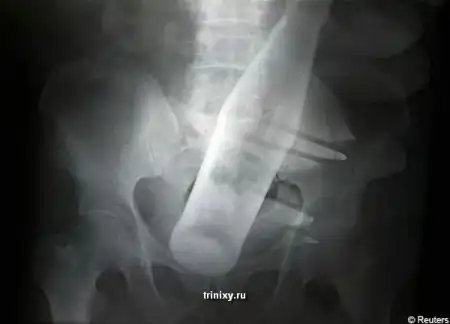

Этот случай произошел в Пакистане. 60-летнего мужчина пришел в больницу и доктор послал его делать рентгеновский снимок. Сам снимок и история в продолжении.

История такова. Грабители хотели украсть буйволов этого пожилого человека. Но он оказал сопротивление и тогда бандиты решили силой забрать скот у него. Чтобы старик согласился в ход пошла стеклянная бутылка из под Pepsi. Она была полностью засунута в задний проход. Естественно бедолага не смог самостоятельно избавиться от инородного тела, находящегося у него внутри и ему пришлось обратиться в больницу. Хирург, обследовавший его , увидев снимок потерял дар речи. Потерпевшему пришлось пройти серьезный курс лечения.